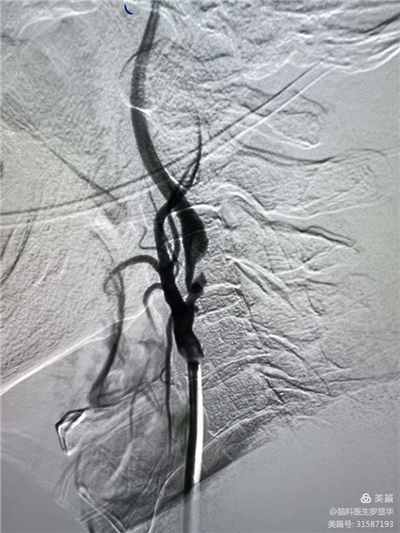

李東波副院長團隊正在為患者行頸動脈支架植入術

手術過程:指引導管到位

手術過程:球囊擴張后,protege支架到位

術后造影示狹窄解除